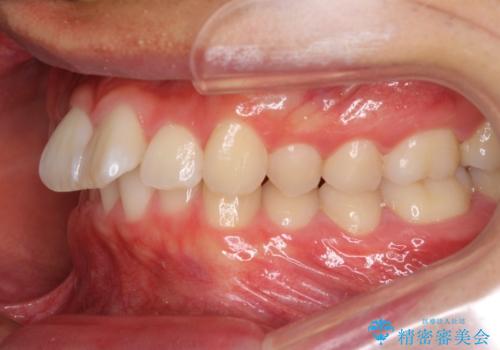

深い咬み合わせとデコボコ ワイヤー矯正で短期治療

インビザラインでの治療も可能でしたが、深い咬み合わせと奥歯の咬み合わせを改善するにあたり、ワイヤー矯正の方が治療期間を短縮できると判断し、ワイヤー矯正をお勧めしました。

結果として、1年かからずに奥歯の咬み合わせを改善することができました。